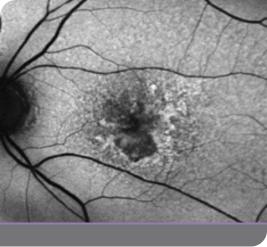

Case study

Case study of a GATHER2 clinical trial patient

This is the experience of a 79-year-old female with bilateral GA who reported good vision but said she needed a magnifying glass to read the newspaper

The patient was enrolled in the IZERVAY clinical trial for treatment of the right eye, and the left eye was observed. 2.5 years after initiating treatment in the right eye, product became available and the left eye was treated with IZERVAY.

• Baseline vision was 20/40 OD and 20/63 OS

• In the right eye, there was a 4.01-mm2 nonsubfoveal GA patch

• In the left eye, there was a 0.77-mm2 patch of GA inferiorly

• Hyperfluorescence at the lesion border signifies disease activity and is an indicator of progression

In this patient, IZERVAY slowed lesion growth over time

Treatment initiated

IZERVAY-treated right eye (OD)

Image of right eye treated with IZERVAY and untreated left eye at treatment initiation

Untreated left eye (OS)

OD=oculus dexter; OS=oculus sinister.

Images courtesy of Dr. Beth Richter.

This is an individual patient case study. It should be interpreted with caution and cannot be considered conclusive. Individual results may vary. In the GATHER trials, sham was used as the comparator.